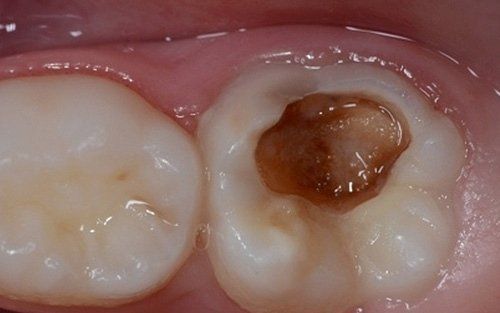

Despite the first signs having been noticed by practitioners at the end of the last century, we can consider the hypomineralisation of molars and incisors (M.I.H. - Molar Incisors Hypomineralisation) as a condition of children in the 2000s. It is characterised by insufficient mineralisation, especially of the first permanent molars, which appear with white-yellowish or brown spots and enamel that is very "porous," lacking the protective shield necessary for the health of these teeth. This leads to a greater tendency for decay, but above all, to structural breakdown of the affected areas under chewing load.